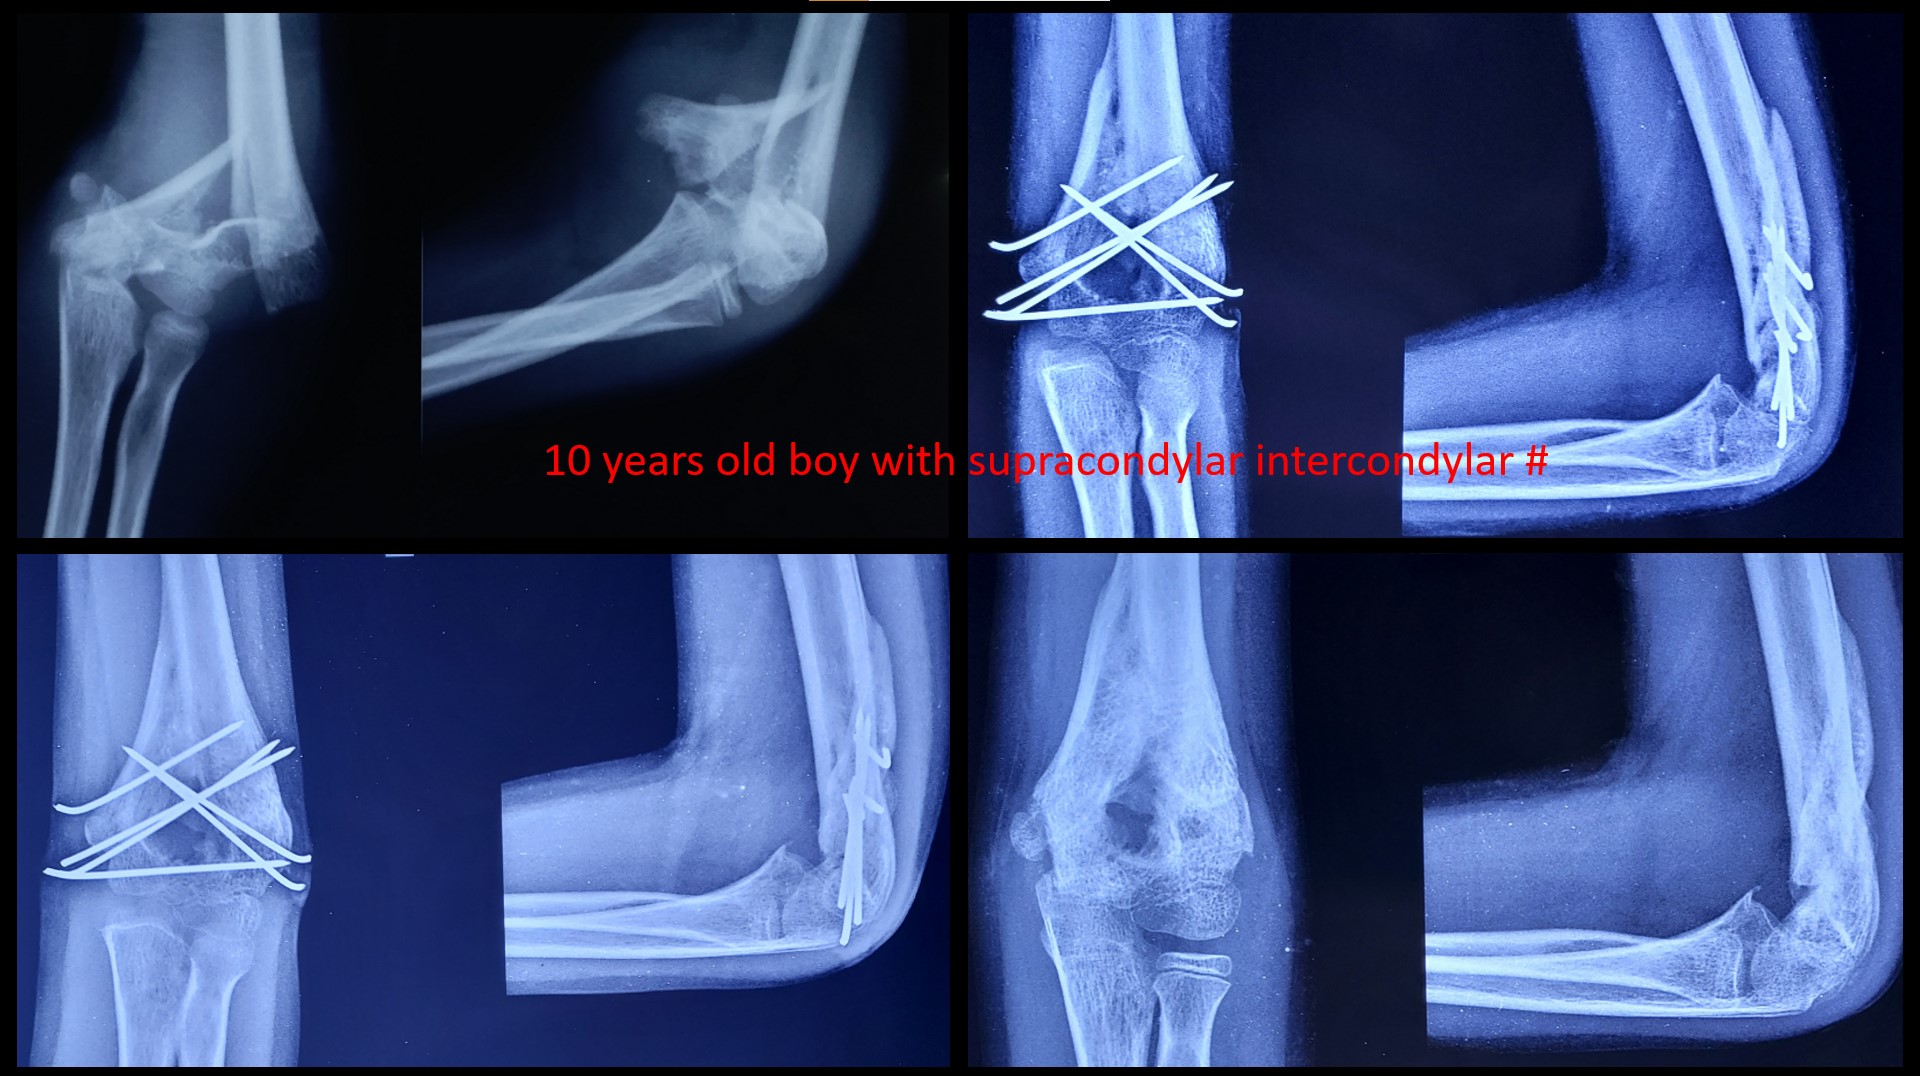

SUPRACONDYLAR #